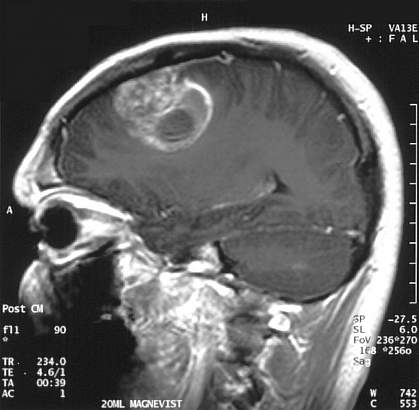

The most common form of malignant brain cancer in adults, glioblastoma multiforme (GBM), has 4 distinct molecular subtypes, according to a new study. The finding may lead to more personalized approaches to treating GBM patients.

GBM is a fast-growing type of tumor. In recent years, 3 of every 100,000 Americans have been diagnosed with GBM—the highest incidence rate among malignant brain tumors. Most patients die of the disease within 14 months of diagnosis.